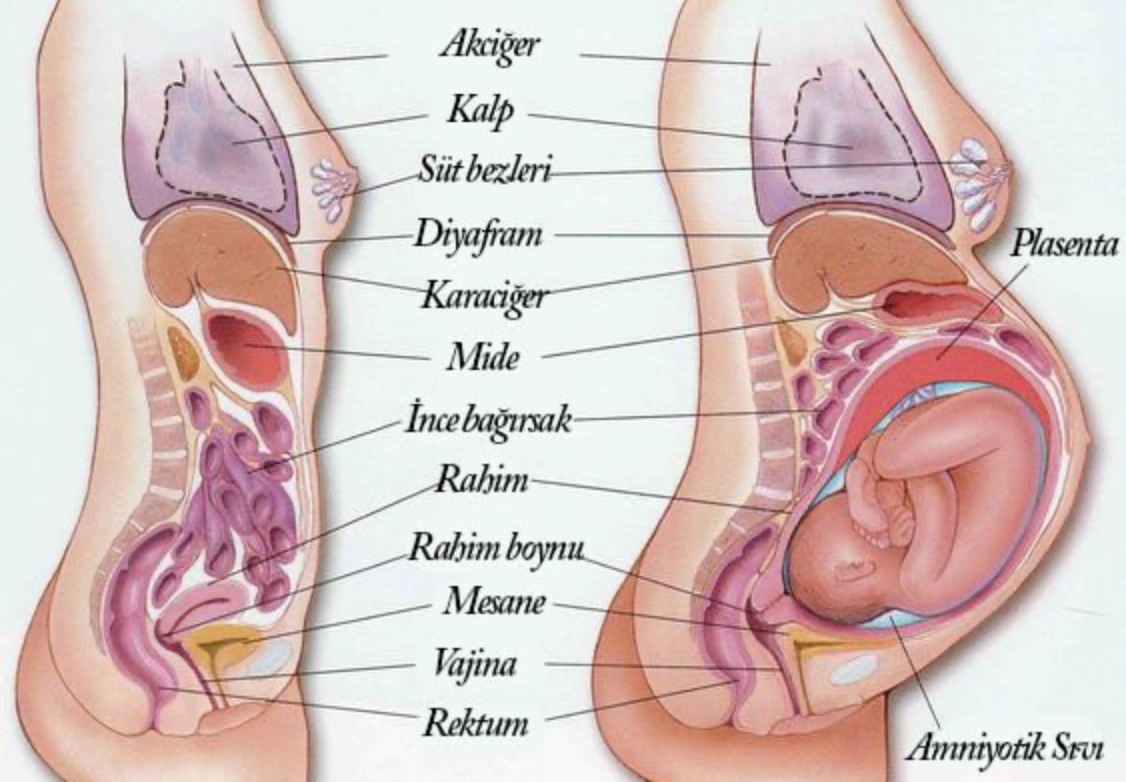

Физиология беременности: строение органов

Раздел: Моменты озарения